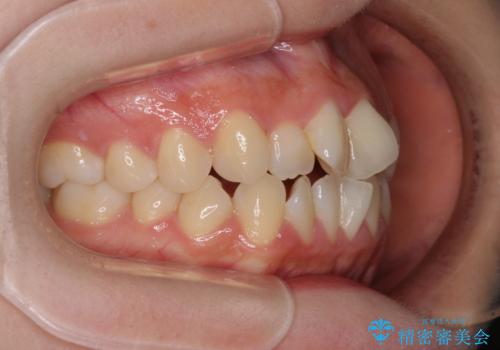

治療開始当初は舌の突出癖が改善されておらず、上下前歯の隙間がより顕著な状態となりました。

舌のトレーニングは、突出癖がなくなるまで必要であり、矯正治療後に突出癖が残ると、あっという間に隙間が空き、後戻りでデコボコとなってしまいます。